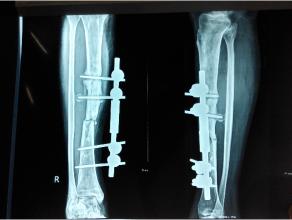

在廣義上,治療計(jì)劃應(yīng)包括改善局部生物學(xué)行為或/和加強(qiáng)其機(jī)械穩(wěn)定性。常用的改善局部生物性狀的治療方法包括:去除感染灶,骨移植,骨髓移植和應(yīng)用Ilizarov方法。提高機(jī)械穩(wěn)定性的方法包括:鋼板螺釘內(nèi)固定術(shù),髓內(nèi)釘內(nèi)固定和外固定架。